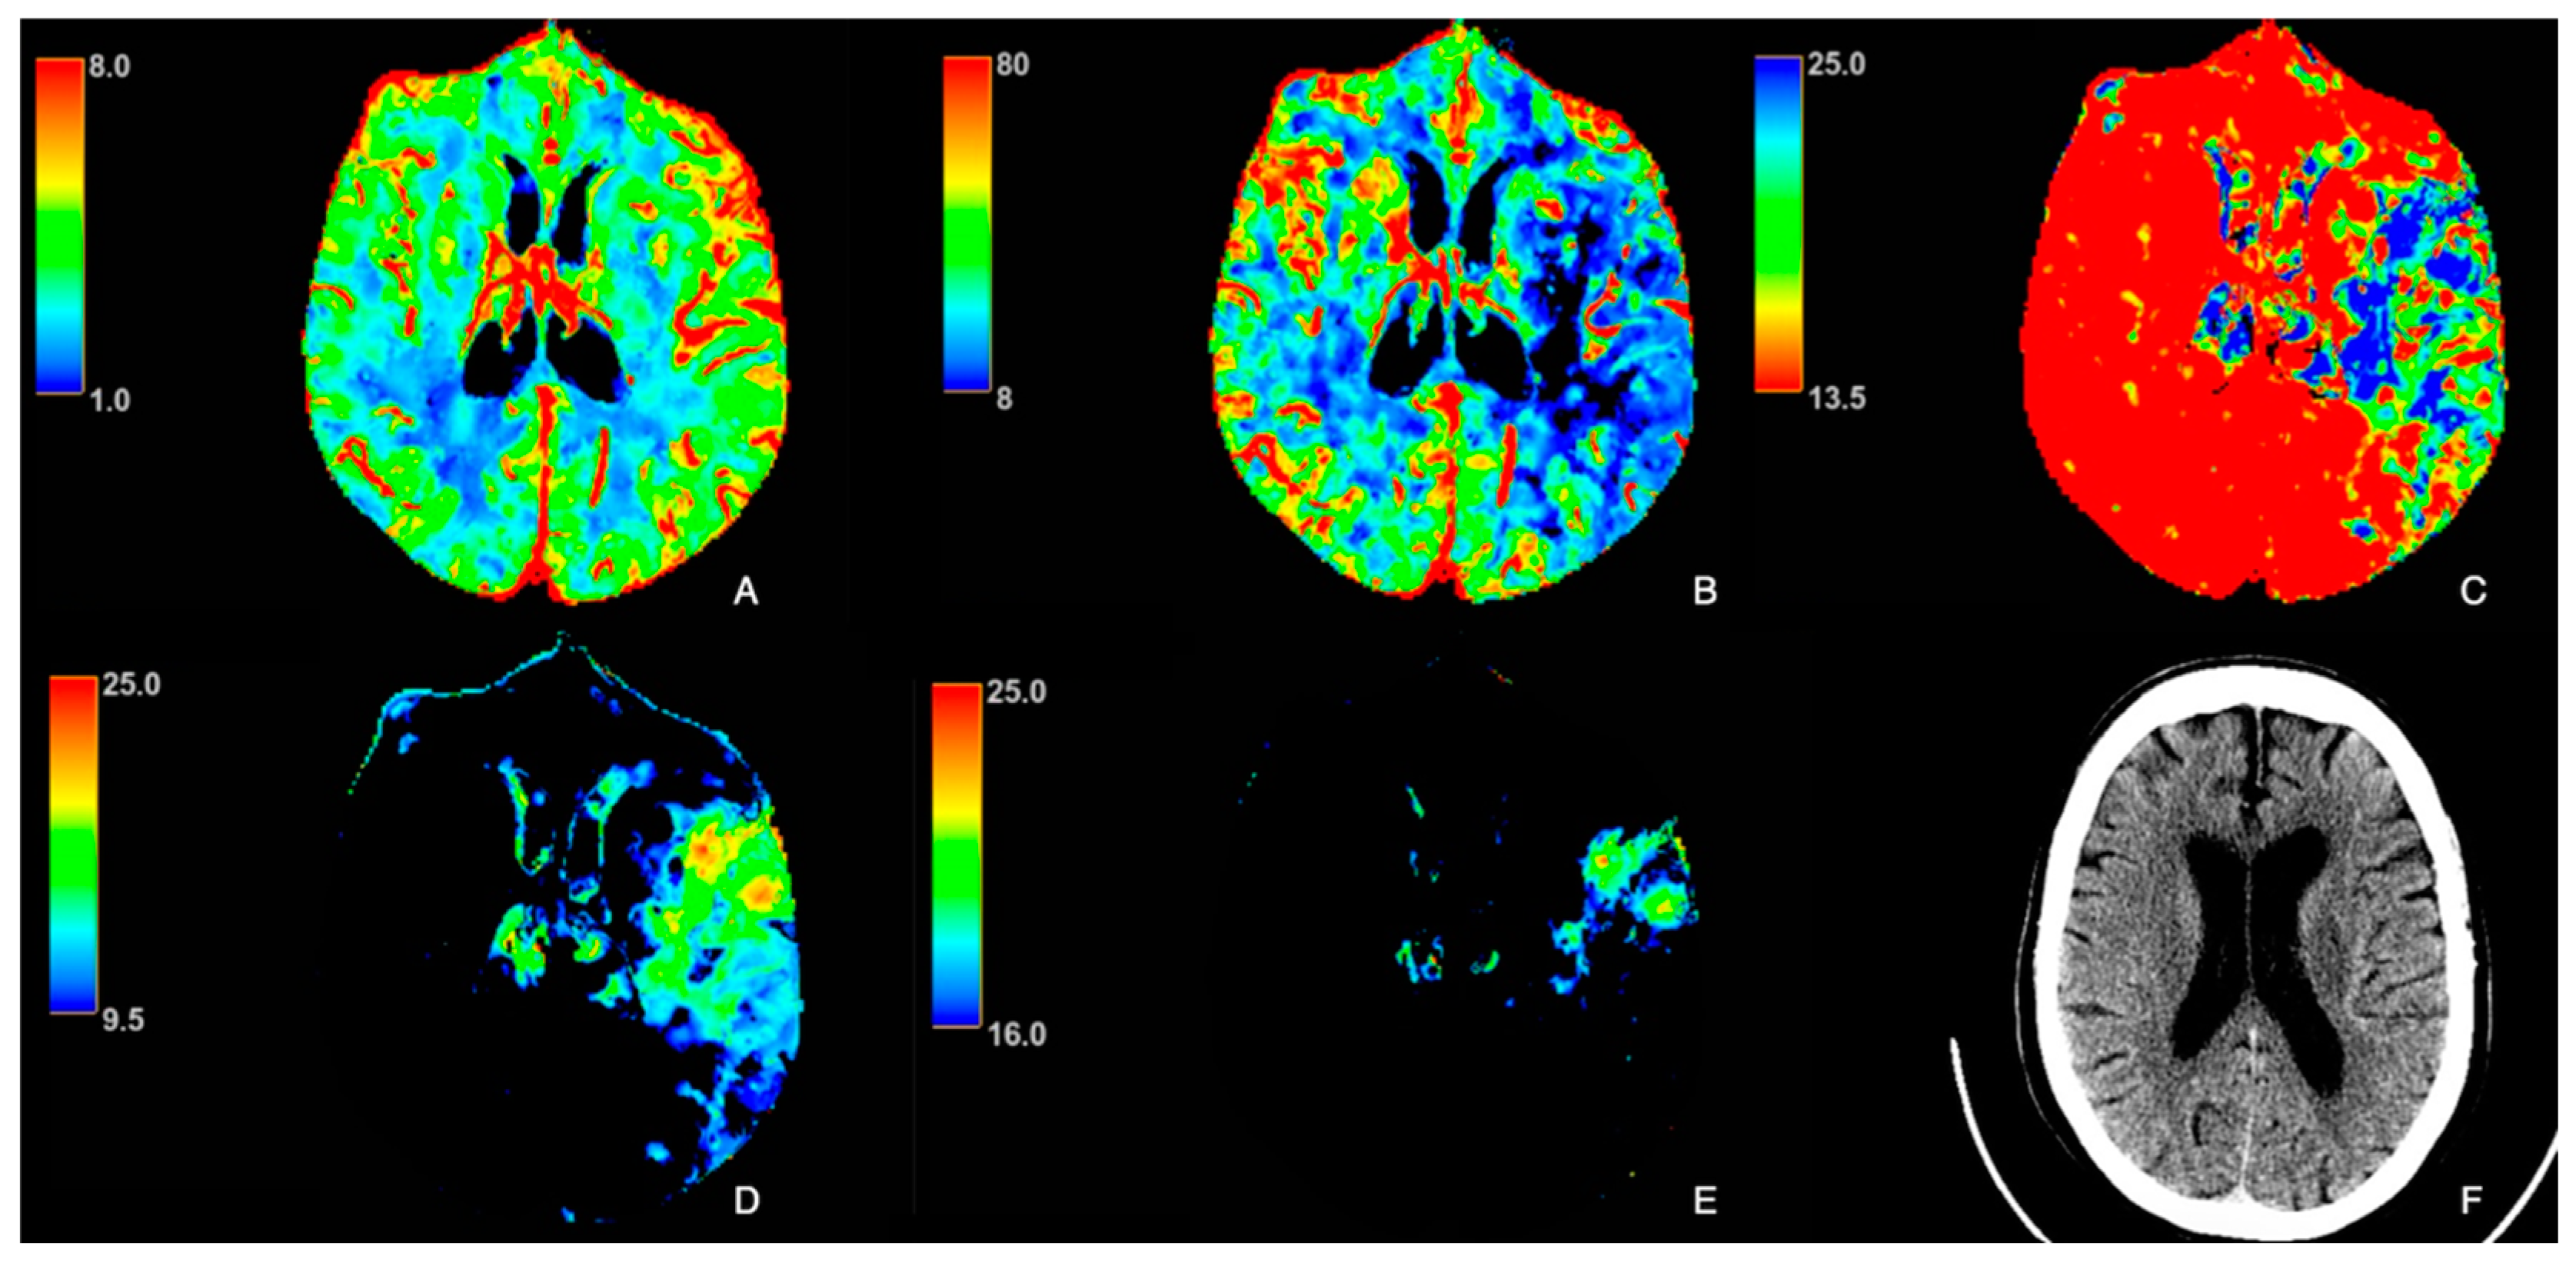

3. Results